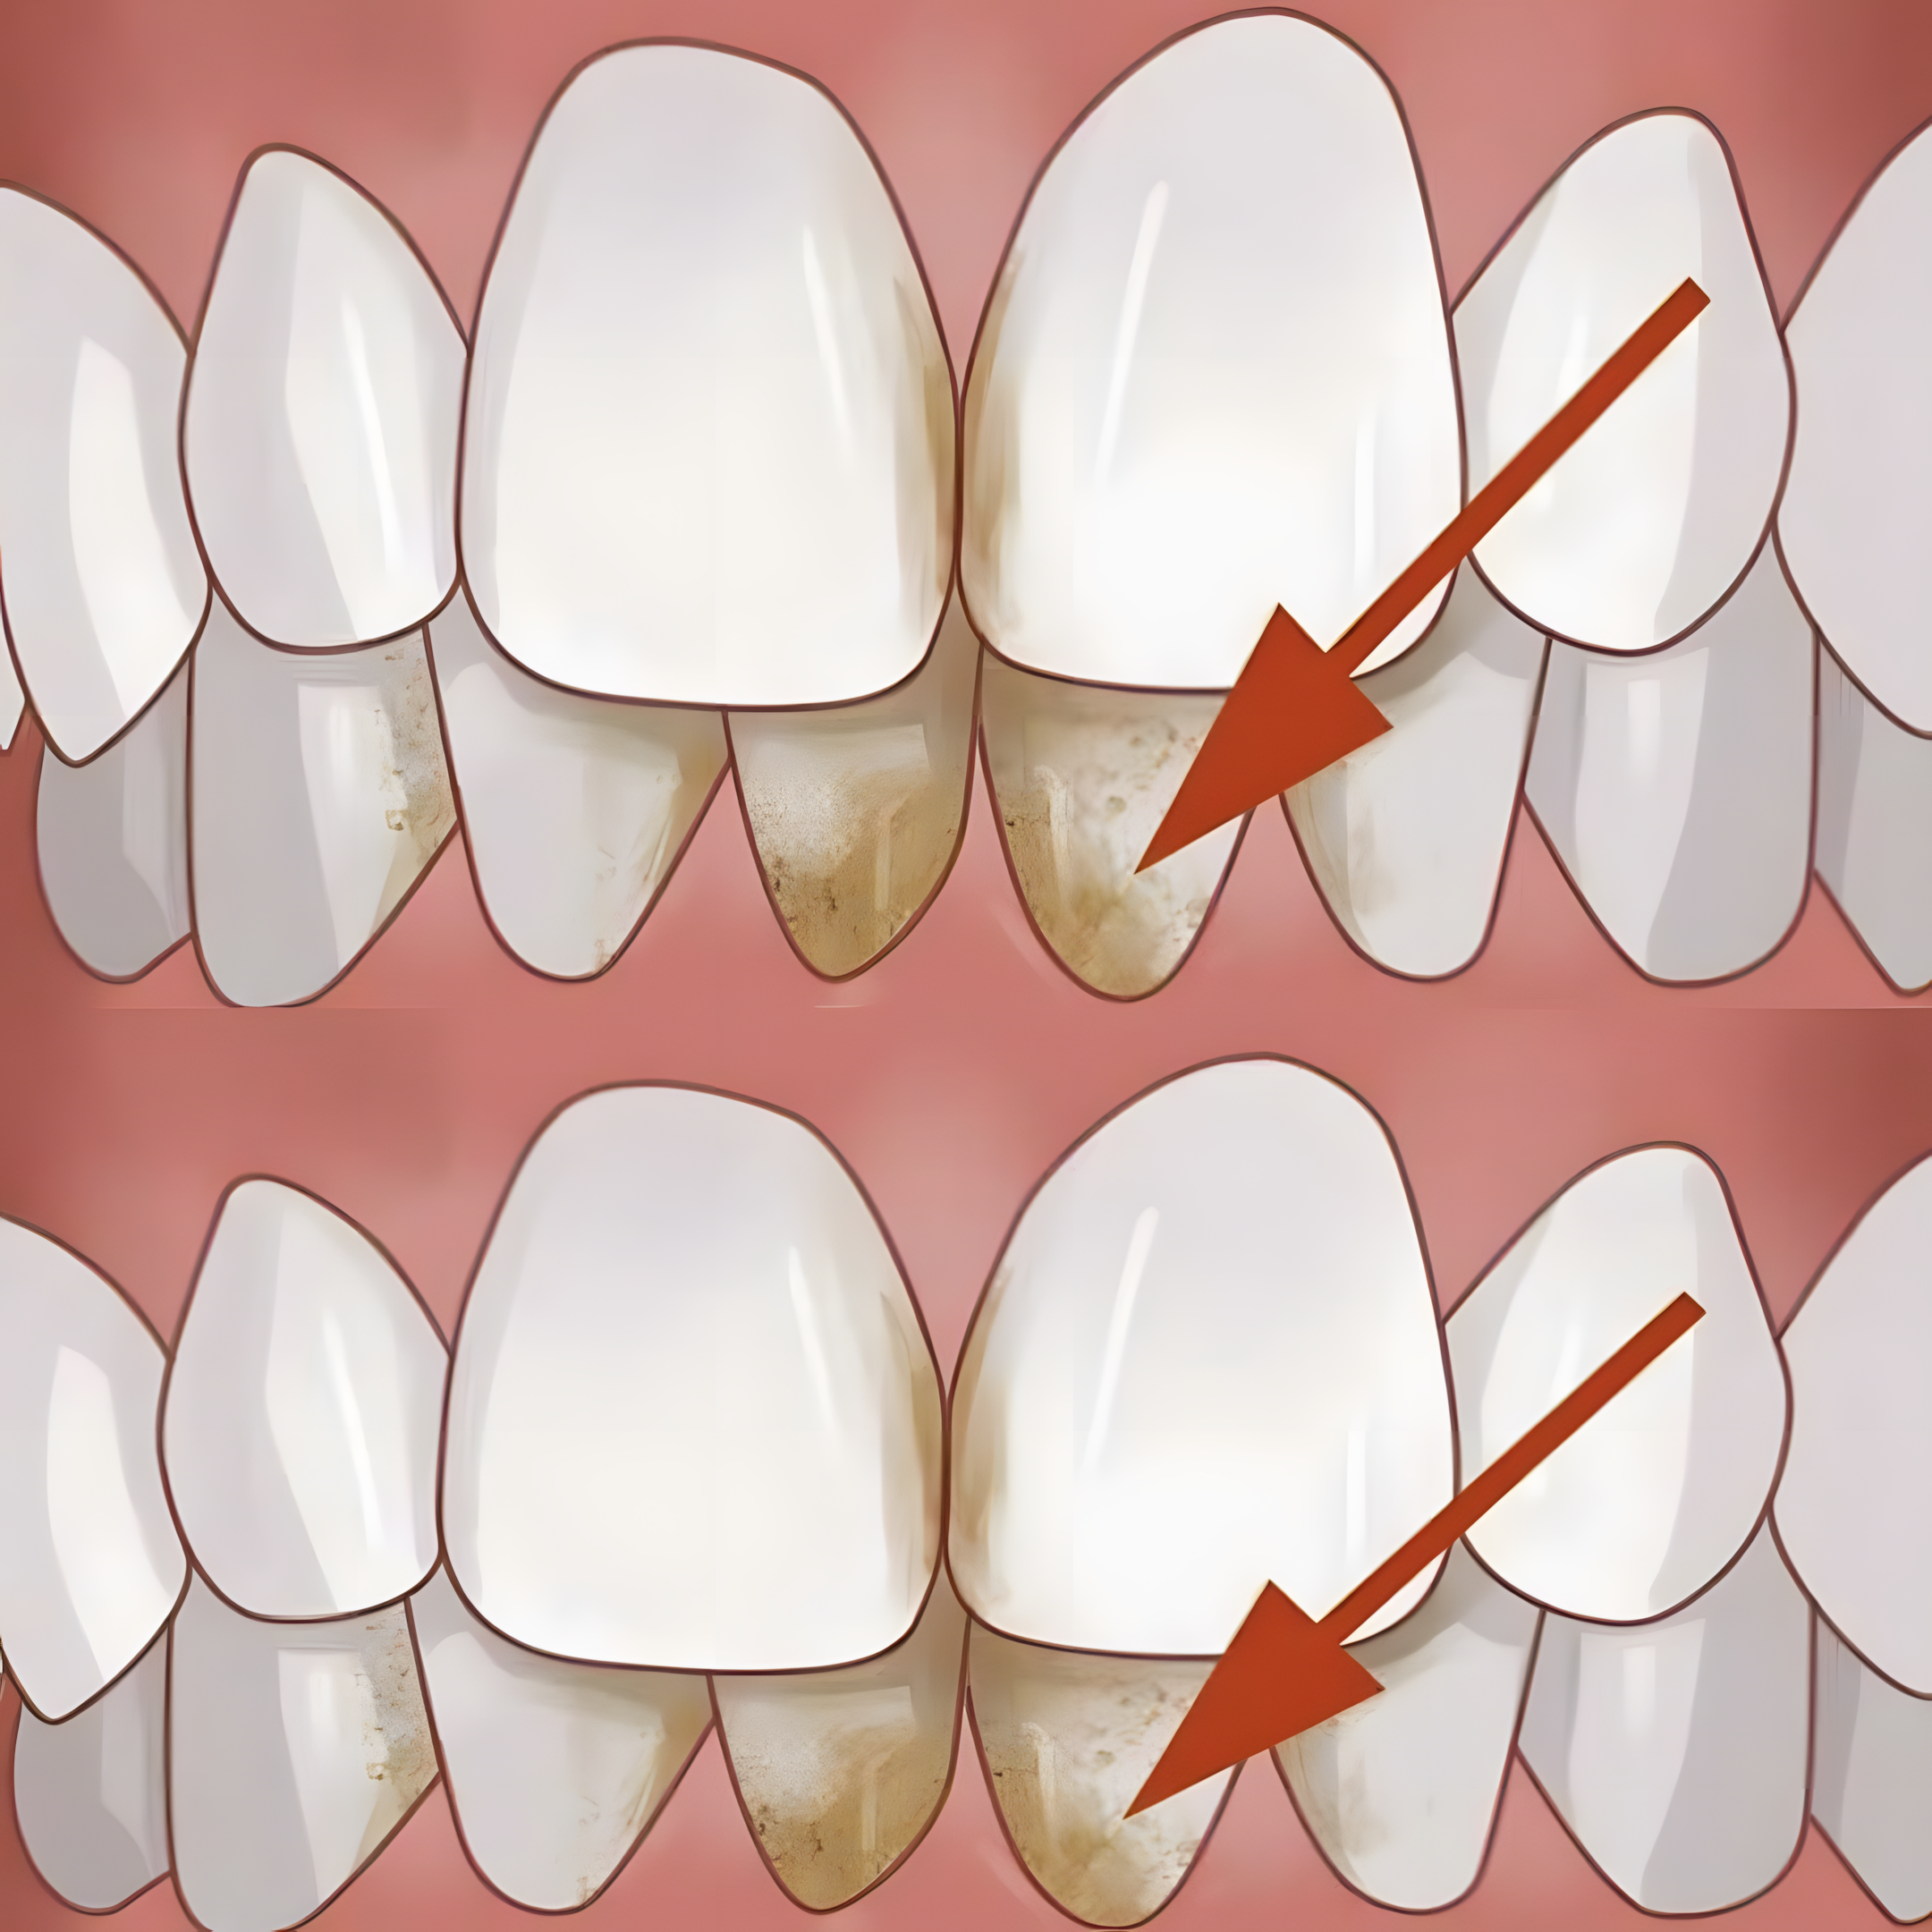

Mondhygiëne is veel meer dan alleen een frisse adem en een witte glimlach. Wat er in je mond gebeurt, heeft invloed op je hele lichaam. En toch kampen miljoenen mensen met een hardnekkig probleem: tandsteen. Het ontstaat wanneer tandplak – dat kleverige laagje bacteriën – niet goed wordt verwijderd en zich verhardt tot een geelachtige, ruwe aanslag. Het goede nieuws? Je hoeft geen fortuin uit te geven aan dure behandelingen, want mijn grootmoeder had een briljante oplossing. En geloof me: die werkt écht.

Tandsteen is niet alleen een esthetisch probleem. Het werkt als een broedplaats voor bacteriën die ontstekingen veroorzaken, leidt tot tandvleesbloedingen, terugtrekkend tandvlees, gaatjes en uiteindelijk tandverlies. Bovendien is het een risicofactor voor hart- en vaatziekten. Regelmatig poetsen en flossen helpt, maar is vaak niet genoeg. Tandsteen nestelt zich juist daar waar je moeilijk bij kunt.